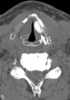

Teflon injection of vocal cord